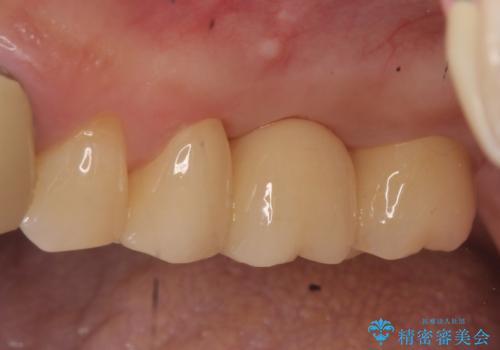

外れそうで不適合のかぶせ物の根管治療からの再治療